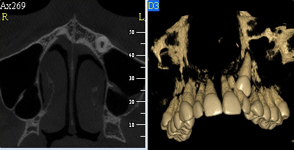

Pomocí tohoto přístroje je možné zjisti skutečnou situaci v čelistních kostech pacienta tedy množství kosti - můžeme změřit skutečnou šířku i výšku kosti, i kvalitu kosti (hustotu) v místě uvažované implantace. 3D (tříprostorové) zobrazení umožňuje

zvýšit prostorovou představu operatéra ještě před vlastní operací a zároveň pacientovi lépe objasnit a ukázat oblast plánovaného zavedení implantátu.

Pacient „neumí číst“ RTG snímky, ale díky 3D zobrazení vidí „svoji skutečnou čelist“ – např. jak je nízká či úzká, vidí průběh nervu nebo velikost čelistní dutiny, což mu umožní i pochopení nutnosti v některých případech provést pomocné zákroky

Lékař si vytvoří všechny typy zobrazení potřebných pro naplánování – tedy 2D snímky (panoramatický), příčné řezy i 3D model.

Vidí zde i důležité anatomické útvary – čelistní dutinu, průběh nervu atd. Po proměření množství kosti – šířky i výšky vybere z databáze vhodný typ implantátu a umístí ho do požadované lokality.

Ihned vidí jeho pozici ve všech 3 rovinách a na všech snímcích i 3D modelu. Může upravovat podle potřeby jeho pozici, sklon atd.